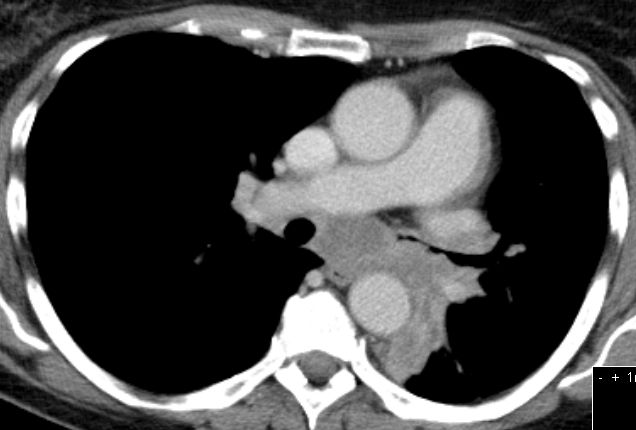

| Lunge | 58-jährige Frau, die vor 3,5 Jahren ein

Endometriumkarzinom pT2 pNo(0/33) Mo G1 hatte. 10 Monate später Pleuraerguss,

pulmonale Metastasen. Jetzt 3. Progress Carboplatin, Taxol, MPA.![]() |